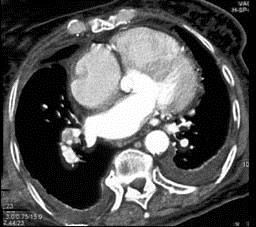

问题 男,38岁,反复咳嗽、咳痰伴发热15年余,痰结核菌素试验(—),结合CT图像,最可能的诊断是 ( )

选项 A.肺癌 B.肺结核 C.肺结节病 D.肺转移瘤 E.肺淀粉样变性

答案 E